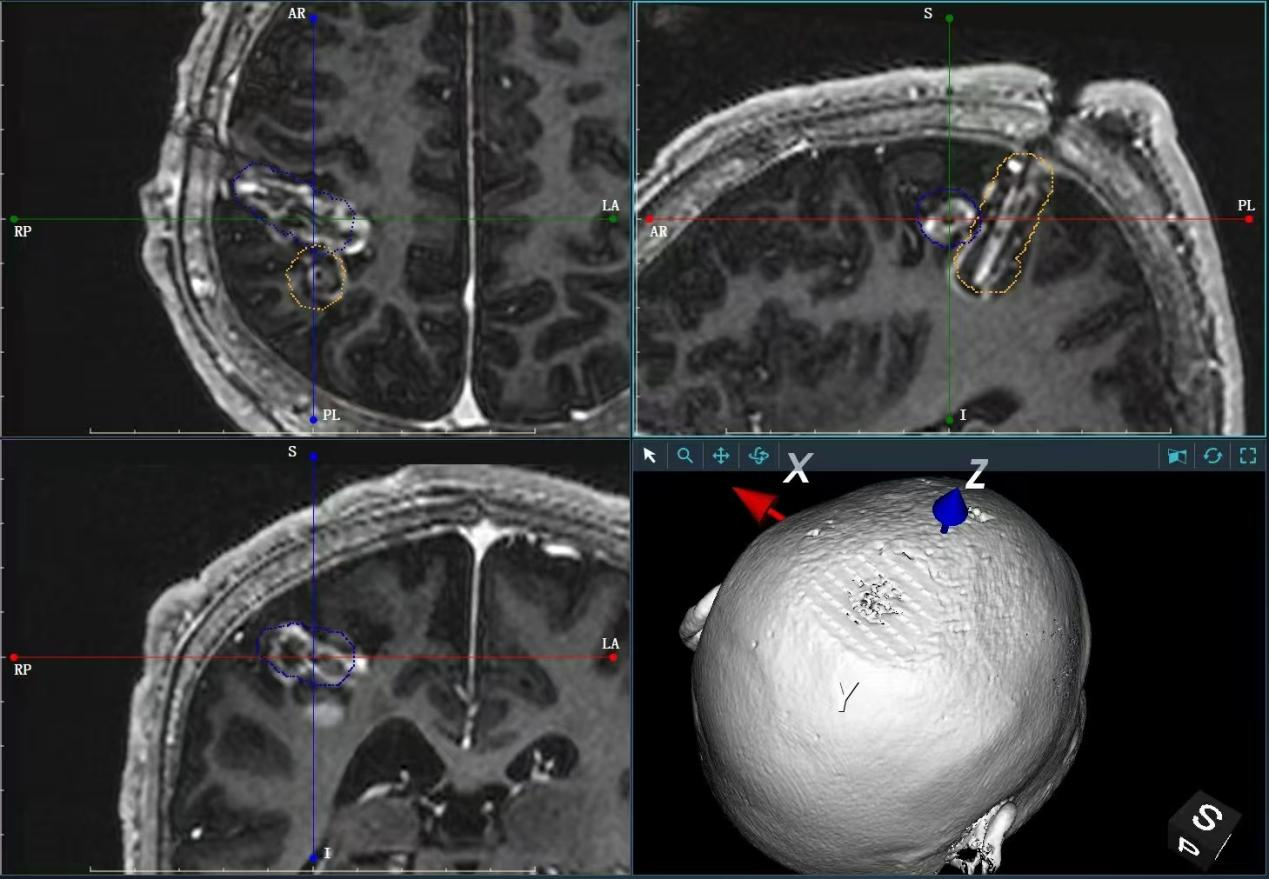

激光治疗过程图示

在消融阶段,系统以41℃~45℃的温度对病灶进行可控加热。术中磁共振连续扫描,实时生成三维温度分布图并投射于手术屏幕,使医生能够同步观察消融范围,确保其严格限定在病灶边界内,不损伤周边正常神经纤维。